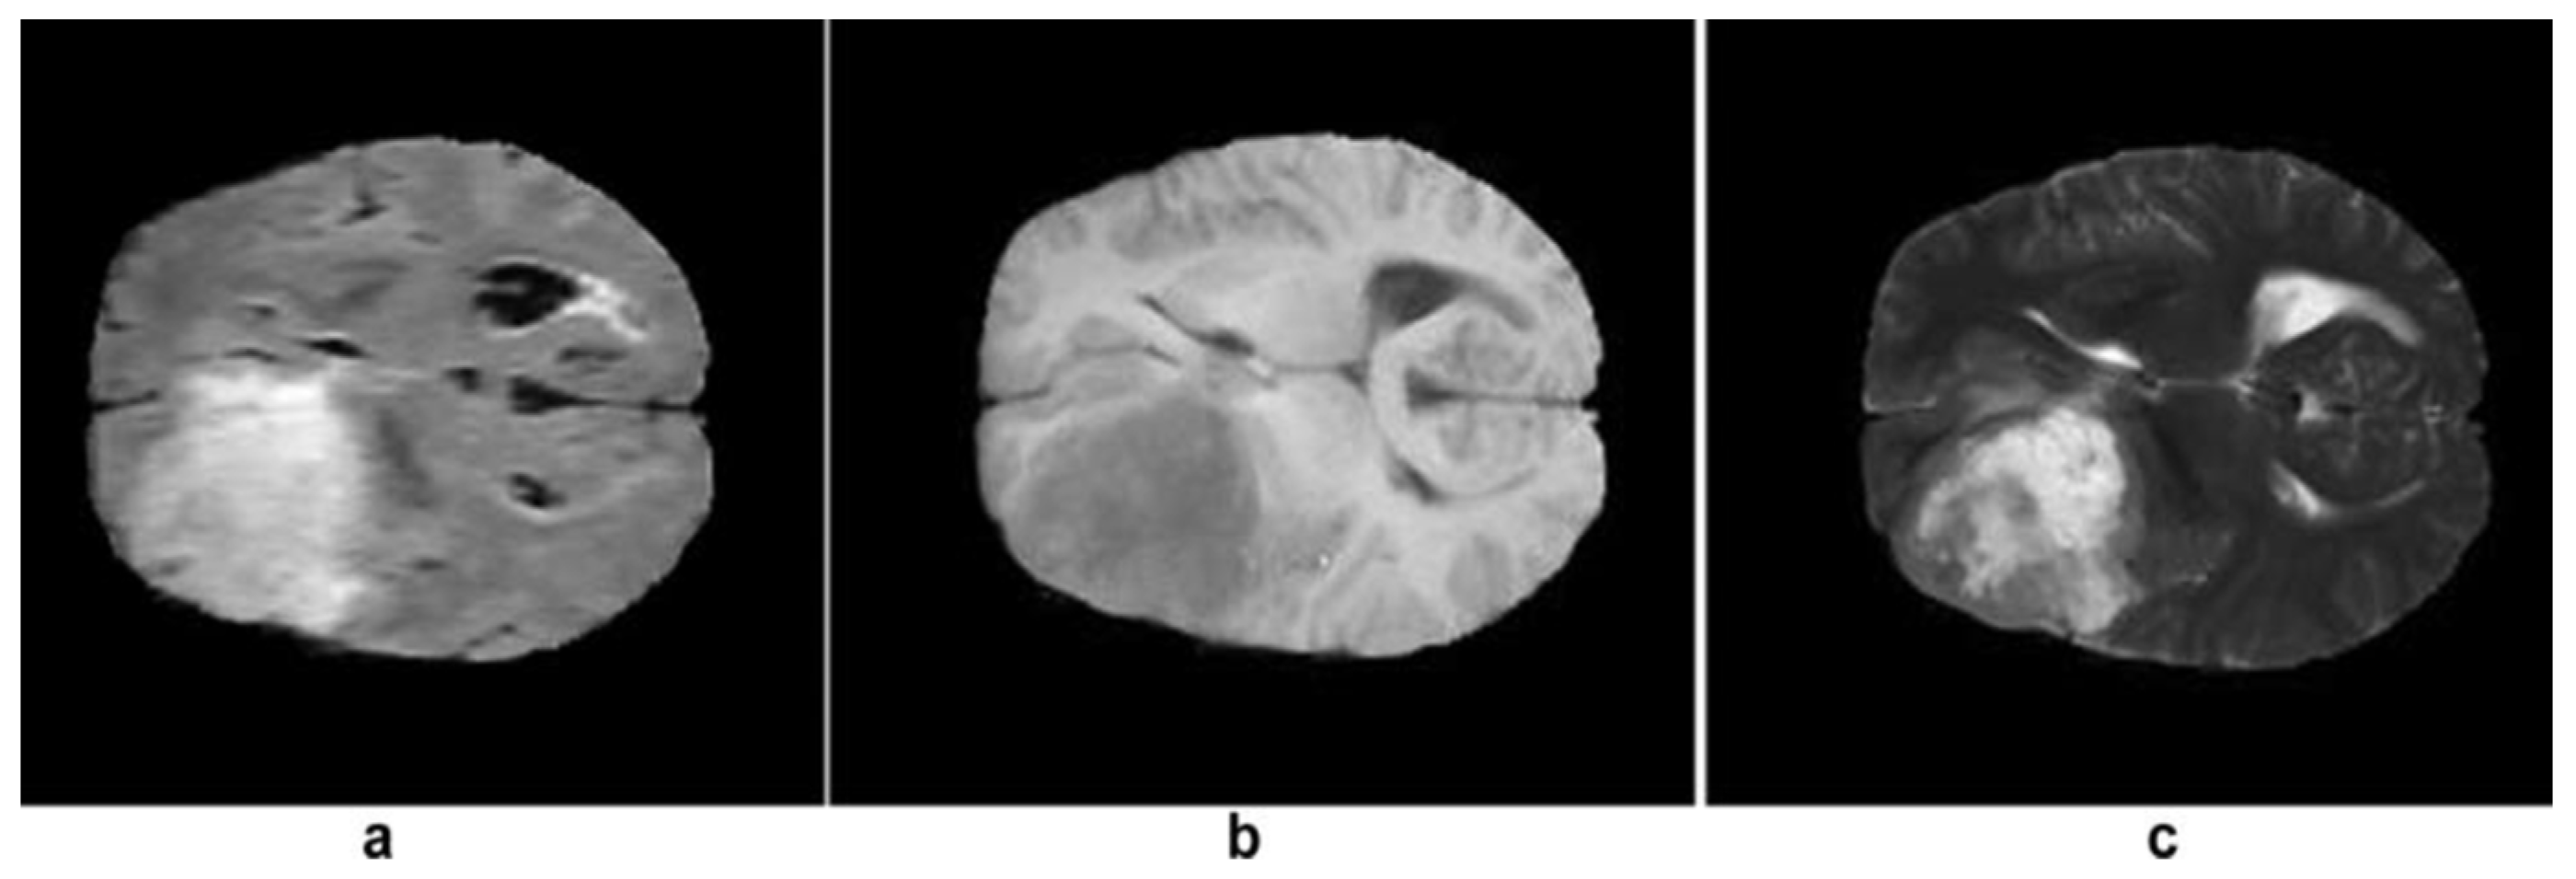

3.1. MRI

| T1 | T2 | Flair | |

|---|---|---|---|

| White Matter | Bright | Dark | Dark |

| Gray Matter | Gray | Dark | Dark |

| CSF | Dark | Bright | Dark |

| Tumor | Dark | Bright | Bright |